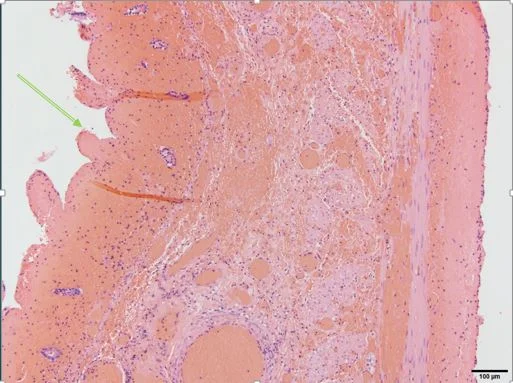

Histopath (courtesy of Dr. Cameron, HCMC): Transmural hemorrhage (all that red stuff) from the mucosal side (green arrow) to the serosa. The loop is completely necrotic.